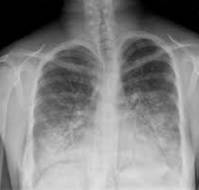

Fulminant pneumonia due to Mycoplasma pneumoniae (MP) is rare, despite the high prevalence of Mycoplasma infections in the general population. We report a case of at..

A report describes a case of a previously healthy 2-year-old girl who presented with six days of productive cough, high fever, and poor appetite. She was fully im..

A 5-month-old female infant was hospitalized due to pneumonia, which quickly progressed to respiratory failure. Immediate intervention included the initiation of non..